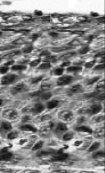

this is?

severe dysplasia, CIN 3

Carcinoma in situ, CIN 3